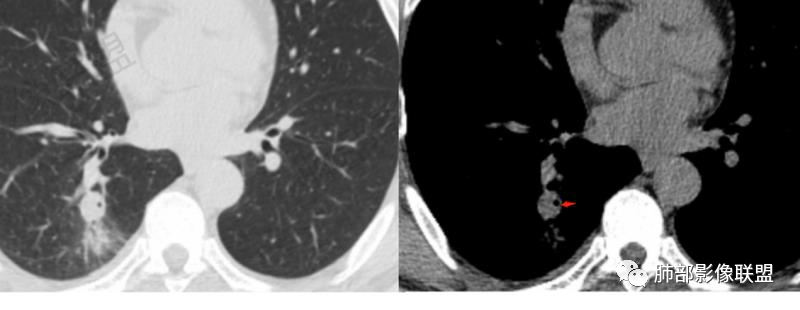

第一次CT:右肺下叶实性结节,近段血管束增粗并与结节相连,结节边缘光滑,密度均匀。第二次(间隔九天,治疗后复查):结节增大,伴有磨玻璃,边界欠清,远端树丫,结节内可见空泡影,壁光滑,临床无明显症状,短期增大先考虑非肿瘤性病变,炎性假瘤,结核,隐球菌。

中年男性患者,1年前发现肺结节,7天前复查结节较前增大,有糖尿病且控制不佳,胸部CT:右肺下叶后段类圆形结节病灶,边界清楚,内部密度均匀,治疗后见内壁光滑的小空洞,结节远端有阻塞性炎症,考虑炎性病变,结核可能,鉴别鳞癌。

右肺结节,气管堵塞,结节边缘光滑,密度均匀,远端斑片影。治疗后复查结节增大,空洞,斑片影伴有磨玻璃,边界欠清,糖尿病,短期增大,考虑结核,隐球菌。

男性病人48岁,既往有糖尿病的病史,影像学表现,右肺下叶后段类圆形的小结节病灶 ,边界比较光整,内见小空洞影 ,病灶远端见小片状的渗出性病灶,增强扫描病灶轻度的强化。病灶在治疗的过程中短期内有增大。整体病灶表现为一个光整结节+远端阻塞性肺炎+小空洞+轻强化,周围无卫星病灶,考虑感染性病变,隐球菌感染?结核次考虑。

右肺下叶结节,边缘光整,密度均匀,伴阻塞炎症,增强无强化,抗感染一周复查效果差,结节内小空洞,阻塞明显,胸膜增厚,糖尿病病史,首先考虑结核,隐球菌待排

糖尿病病史,右肺下叶结节,边缘光整,密度欠均匀,远端阻塞炎症,增强强化不明显,抗感染一周复查,结节较前增大,内出现小空洞,阻塞明显,胸膜增厚,首先考虑结核,隐球菌待排。